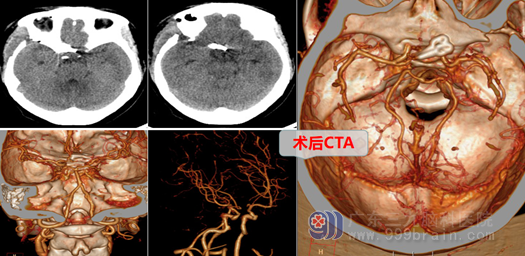

入院后,神经外十科主任欧阳辉教授仔细查看病人及其影像资料,结合病史,认为颅内前交通动脉诊断明确,属较大、宽颈、复杂疑难、高危的破裂动脉瘤。神经外十科团队迅速完善相关检查,由欧阳主任主刀周六急诊在全麻下实施右侧翼点入路、前交通动脉瘤夹闭术+右侧脑室外引流术,术中在高清荧光显微镜下,仔细分离出双侧大脑前动脉A1段和A2段,精确夹闭动脉瘤颈,保持载瘤动脉通畅,保护好视神经和视交叉,最终顺利夹闭了破裂的动脉瘤。

术后未发生明显并发症及后遗症,成阿姨迅速恢复,精神越来越好,已于近日顺利出院。